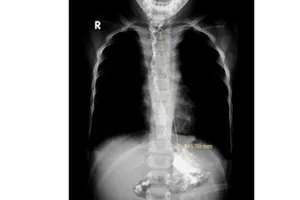

Giật mình khi đang ăn, người đàn ông bị mảnh xương cá diêu hồng cắm vào dây thanh quản 20/04/2022 13:53